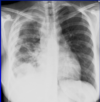

Q

What is this ?

A

How well did you know this?